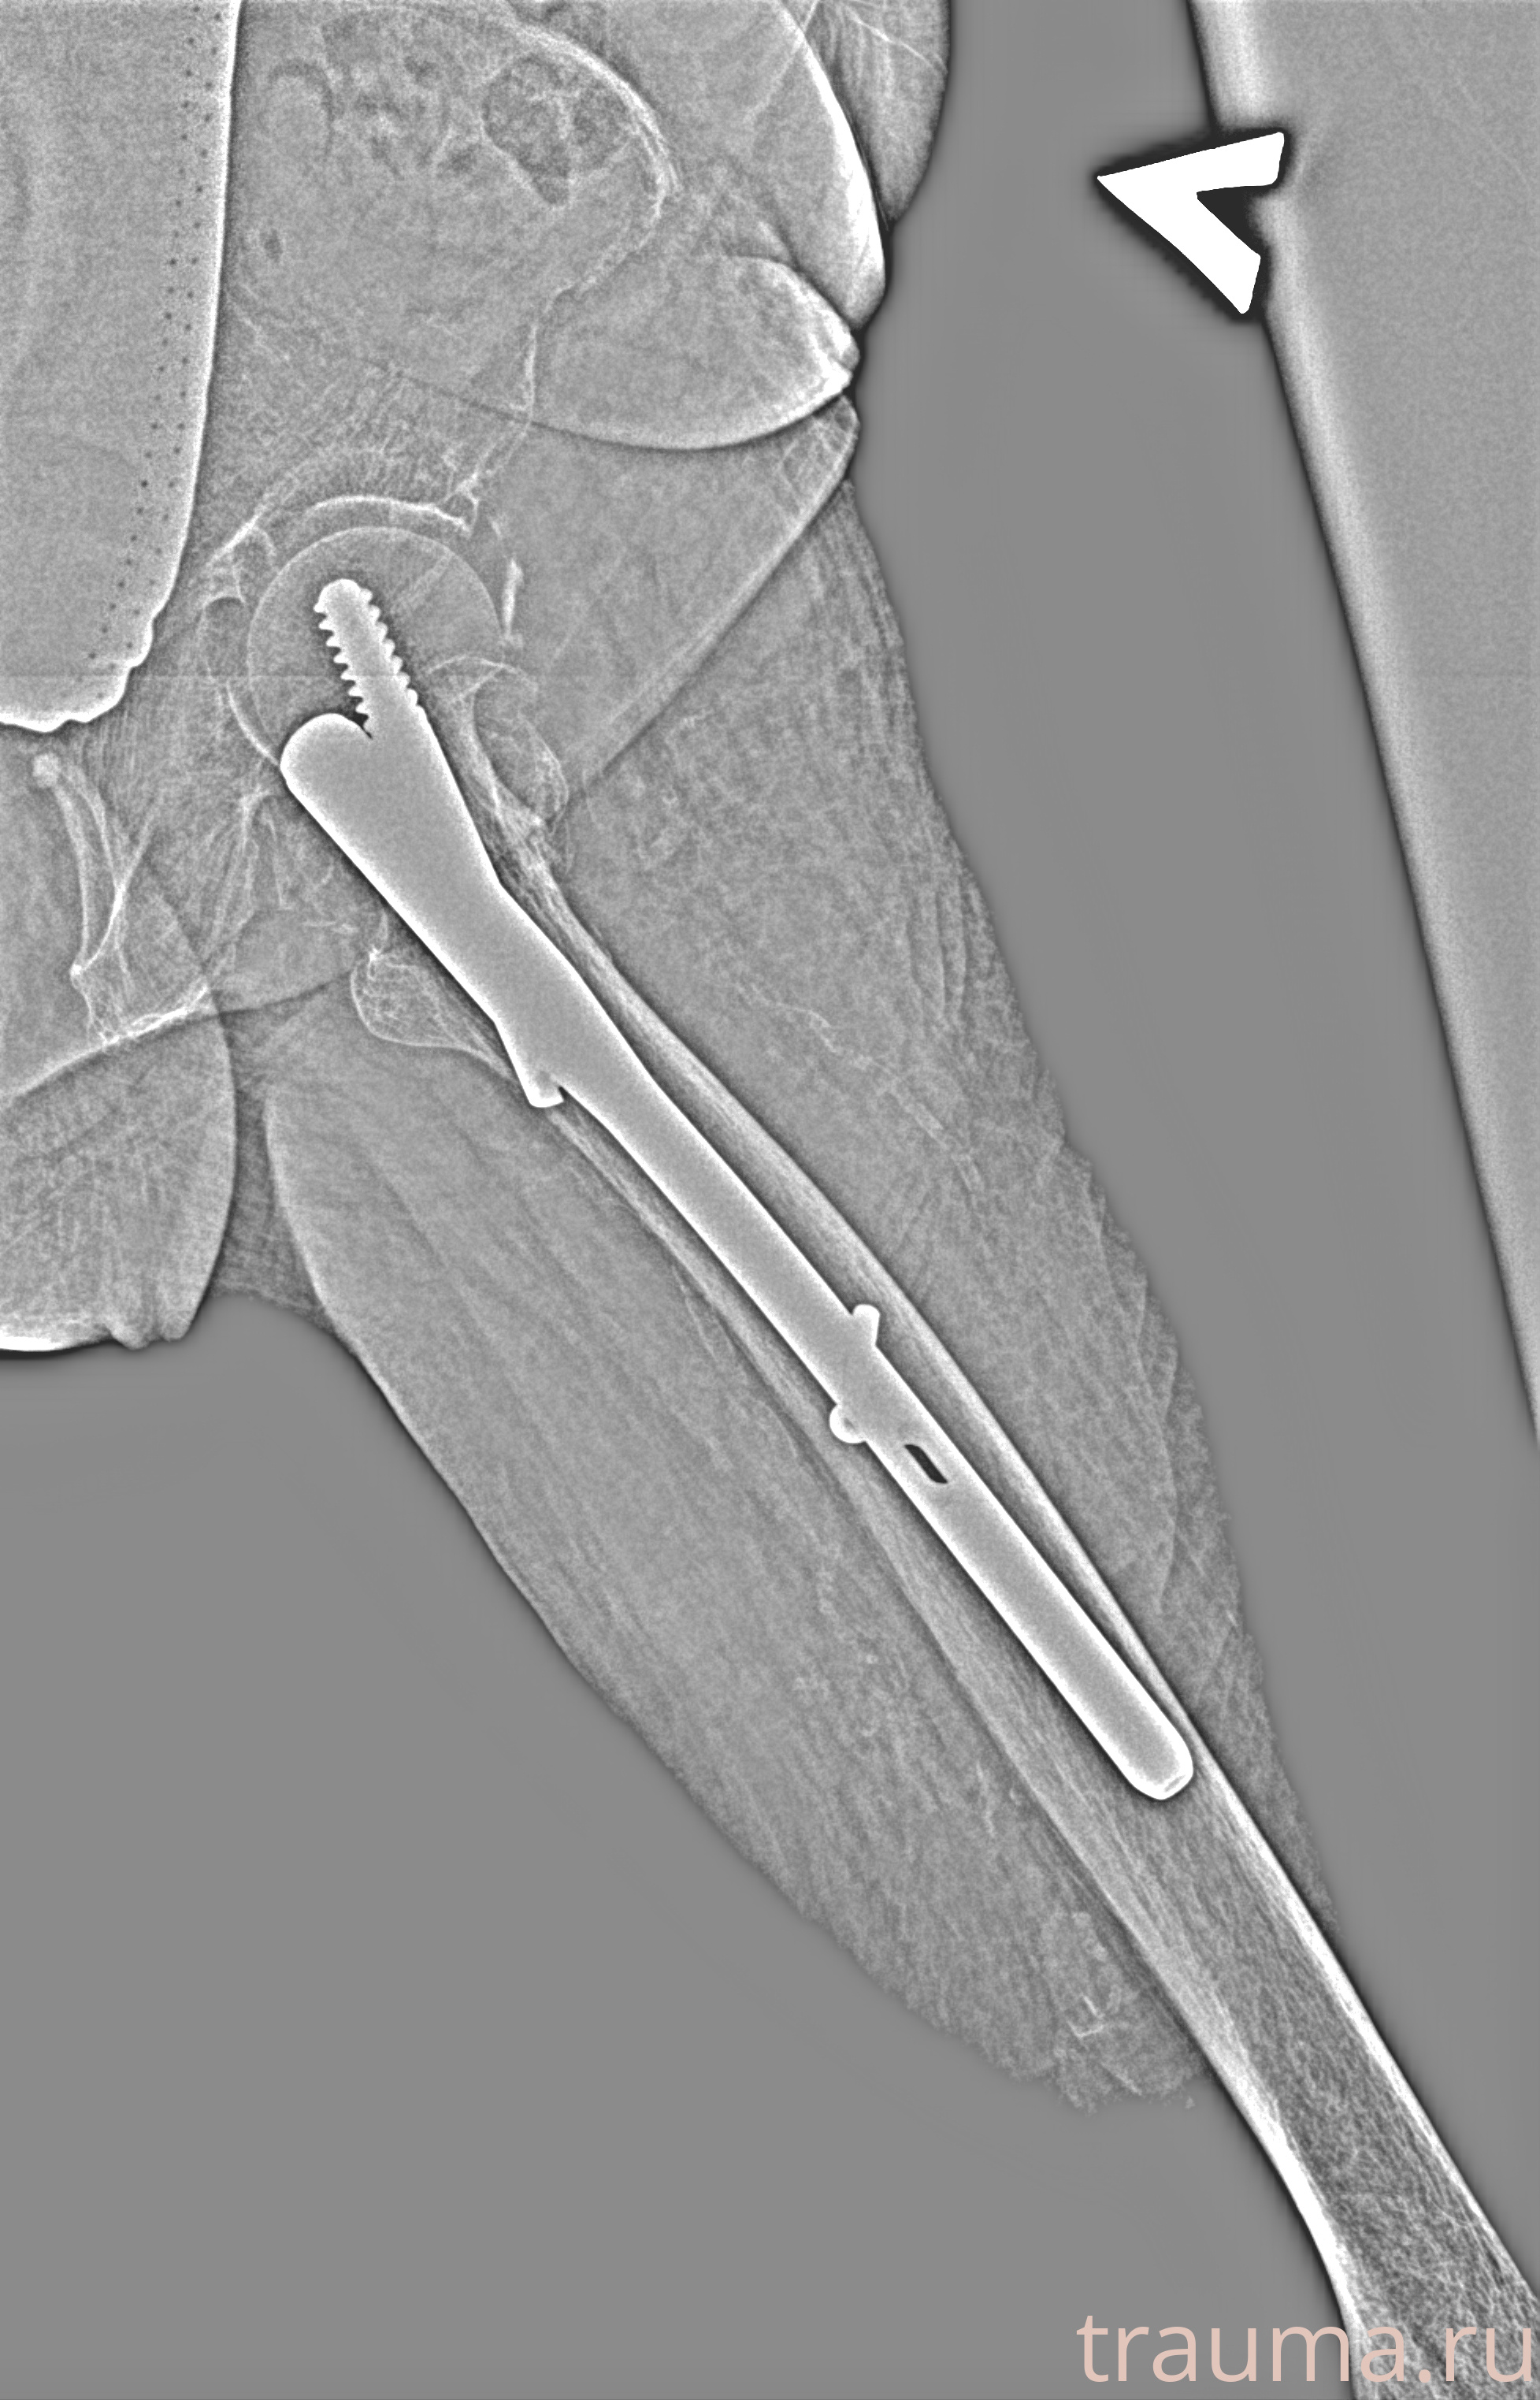

Рентгенограммы

Рентген на дому: по вашему адресу приезжает врач-рентгенолог, травматолог-ортопед с мобильным рентгеновским аппаратом, проводит диагностику травмы или заболевания, делает необходимые рентгенограммы, дает рекомендации по дальнейшему лечению. Получить качественные снимки в домашних условиях возможно благодаря уникальной методике, разработанной МосРентген Центром для института  Склифосовского